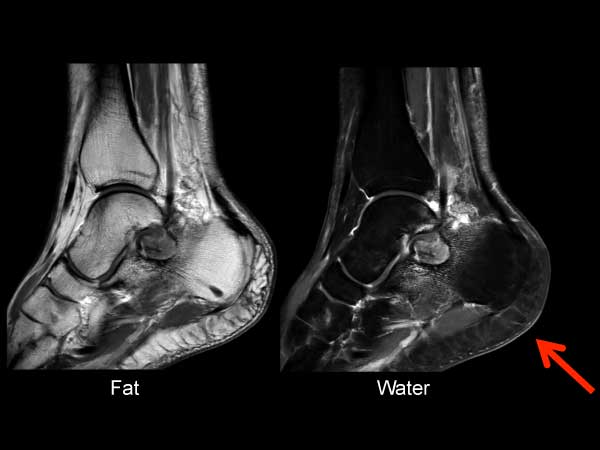

Sagittal T2w mDIXON